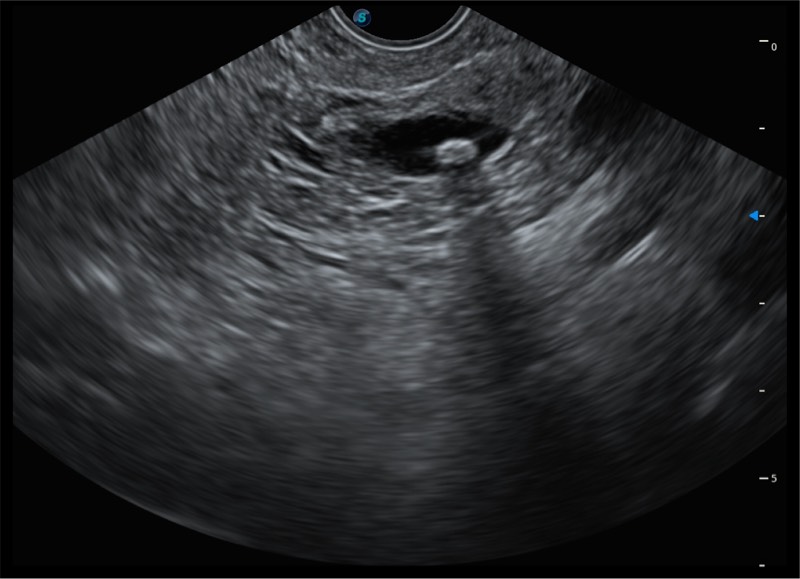

• 搭载百万级CMOS成像技术

• 及自主研发凸阵换能器,

• 可呈现优质的内镜和超声画面

基于二十年的超声技术积累,16877太阳集团提供了最新一代的独立超声主机,在提供高质量图像的同时满足多学科使用。具备常见多普勒技术并提供弹性成像、声学造影等高端影像技术。新一代传感器具有更强的抗干扰能力并减少图像伪影。

• 4.0mm大钳道

• 12.6mm先端部外径

• 150°超声扫描角度

• 4-12MHZ宽频输出